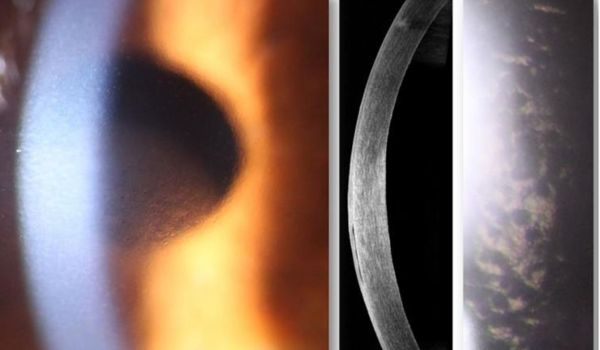

Дистрофії рогівки та кератектазії